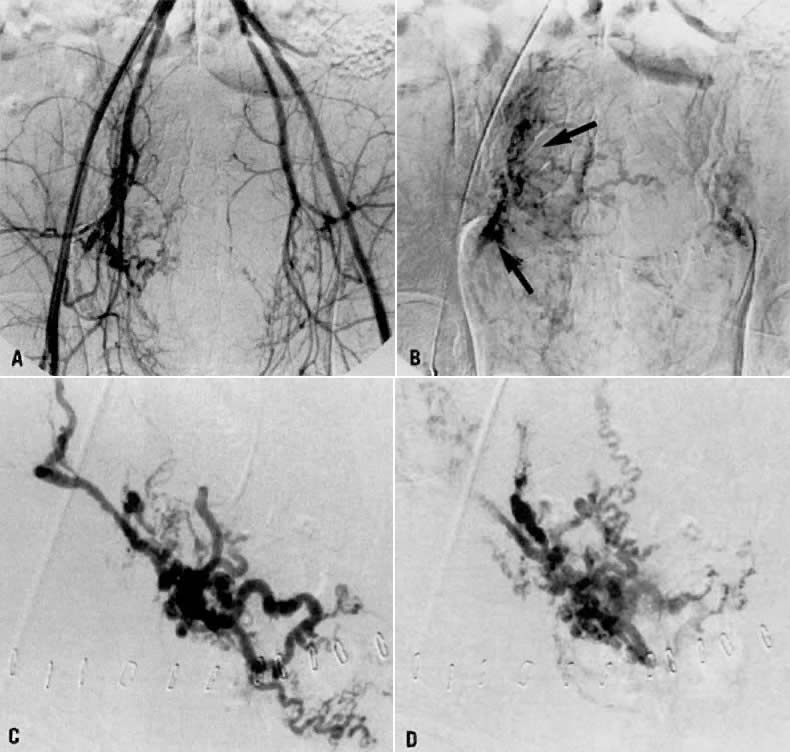

Case 4.

This 30-year-old woman (gravida 3, para 3) required cesarean section at 42 weeks. Despite what appeared to be complete removal of the placenta, the patient continued to bleed from the placental site after surgery, and placenta accreta was considered a diagnostic possibility. To avoid a hysterectomy and to preserve reproductive function, uterine embolization was requested. Anteroposterior pelvic arteriography (Fig. 21A) showed enlargement of the right uterine artery with persistence of contrast enhancement in the late phase (Fig. 21B). Selective right uterine arteriography (Fig. 21C) also showed enlargement of the right uterine artery with typical postpartum changes of the spiral endometrial arteries and dense staining in the late phase (Fig. 21D). Both right and left uterine arteries were embolized successfully and without complication. This intervention produced prompt cessation of bleeding.

Fig. 21. Case 4. Postpartum bleeding resulting from presumed placenta accreta. A. Anteroposterior pelvic arteriogram showing enlargement of the right uterine artery. B. Late-phase contrast enhancement of the same area ( arrows ). C. Right uterine arteriogram showing similar changes. D. Dense staining is shown in the late phase.